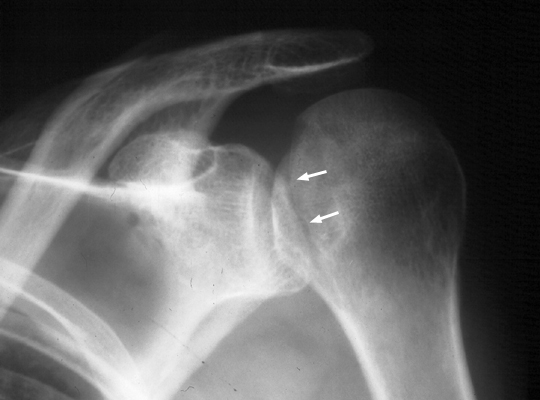

Posterior shoulder dislocation

Trough line is seen with posterior shoulder dislocation. When the humeral head is forced posteriorly in internal rotation, the anterior aspect of the humeral head is driven against the posterior glenoid rim. With sufficient force, the head will sustain a compression fracture. In many cases of posterior dislocation of the shoulder, two parallel lines of cortical bone can be seen. The outer (more medial) cortical line represent the medial cortex of the humeral head, while the other line represents the margin of a "trough" like impaction fracture.